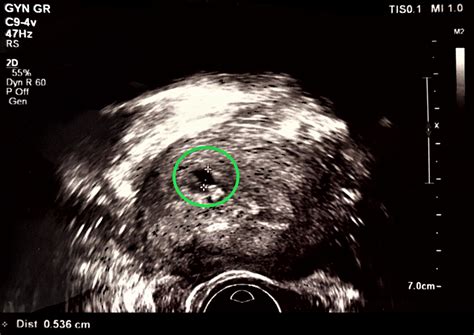

Cornual Ectopic Pregnancy

A cornual ectopic pregnancy is a rare but potentially life-threatening complication of pregnancy that requires immediate medical attention. Unlike a standard ectopic pregnancy, where the fertilized egg implants in the fallopian tube, a cornual pregnancy occurs in the cornua—the upper, lateral area of the uterus where the fallopian tube enters the uterine cavity. Because this area is highly vascular and capable of expanding slightly more than the narrow fallopian tube, these pregnancies can progress further than other types of ectopic pregnancies before they are discovered. However, this also means that when they do rupture, they can result in severe, rapid, and catastrophic hemorrhaging, making early diagnosis and prompt management essential for patient survival and reproductive health.

Diagnosing a cornual ectopic pregnancy is notoriously difficult because, in the early stages, it can appear similar to a normal intrauterine pregnancy or a standard tubal ectopic pregnancy on initial ultrasound scans. Because the cornua is part of the uterine structure, the pregnancy can remain asymptomatic longer than a tubal pregnancy, leading to a false sense of security.

• cornual ectopic measurement

• cornular ectopic pregnancy ultrasound